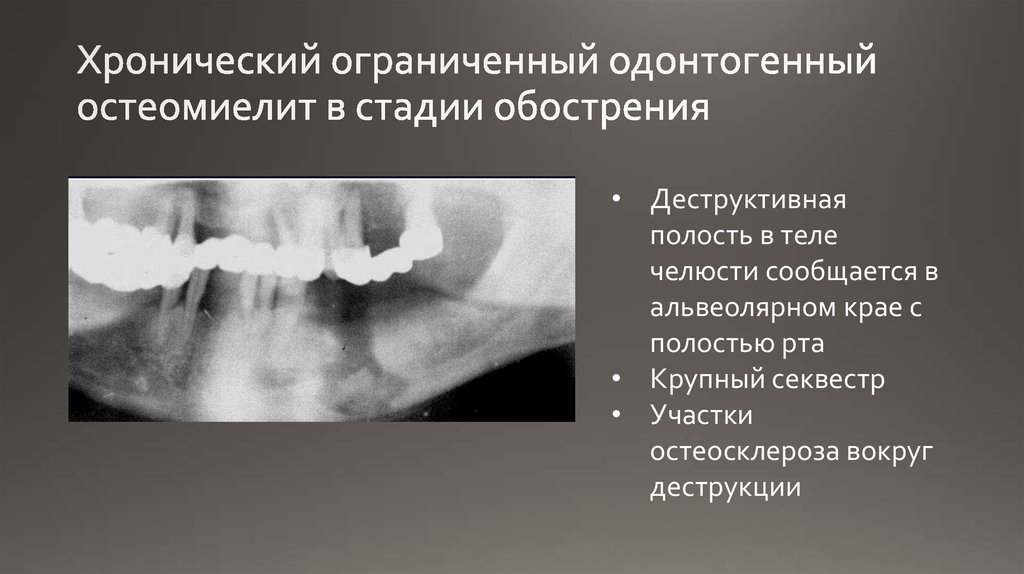

Рентгеновские снимки посттравматического остеомиелита челюсти: Медицинские случаи

Раздел: Образы вокруг